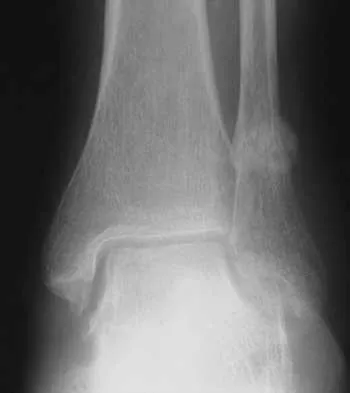

A previously asymptomatic 14-year-old girl sustained a twisting injury to her ankle. Radiographs are shown in Figures 2a and 2b. Management should consist of

The radiographs show a well-defined, irregular, eccentric lesion in the distal tibia metaphysis with a thin sclerotic margin. The radiographs are diagnostic of nonossifying fibroma, a common entity in this age group and in this location. No further work-up is indicated. The patient was asymptomatic prior to the injury and the lesion is small and thus not worrisome for an impending pathologic fracture; therefore, no treatment is indicated beyond observation. The natural history of these lesions is to gradually ossify as the patient reaches skeletal maturity. Menendez LR (ed): Orthopaedic Knowledge Update: Musculoskeletal Tumors. Rosemont, IL, American Academy of Orthopaedic Surgeons, 2002, pp 69-75.